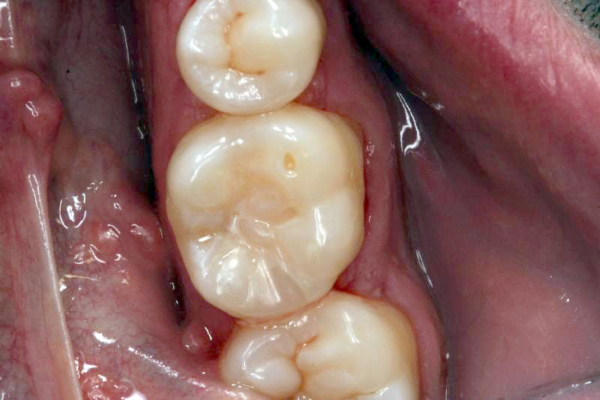

Click on an image below to enlarge & view caption.

Dentistry and photography courtesy of Dr. Robert Margeas.